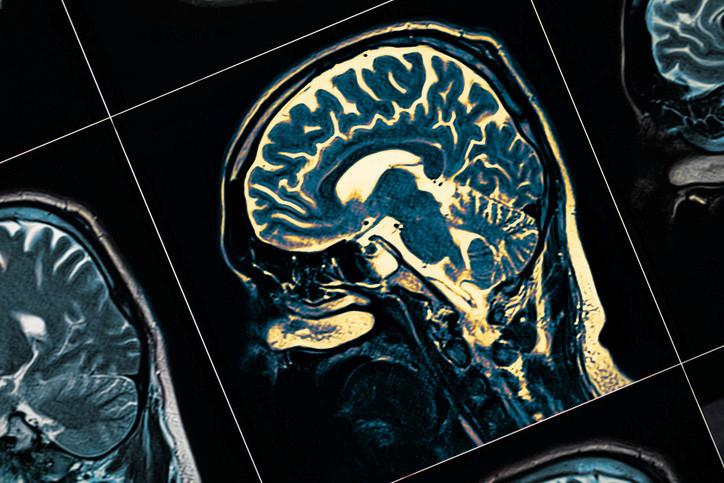

Demans, günlük yaşamda ciddi etkiler yaratabilen, bilişsel fonksiyonlarda ve düşünme yetisinde ilerleyici bozukluk anlamına gelir. Sinir hücrelerinin tahribatıyla gelişen bu sendrom, genellikle normal yaşlanmanın ötesinde bilişsel düşüşler şeklinde ortaya çıkar. Bu durum, ruh hali, duygudurum ve davranış bozukluklarına da eşlik edebilir.

Demansın erken dönem belirtileri arasında, yeni öğrenilen bilgilerin unutulması ve olayların karışıklığı yer alır. Eşyaların kaybolması, zaman ve yer karışıklığı, kelime bulma güçlüğü ve karar verme zorlukları dikkat edilmesi gereken işaretlerdir. Ayrıca, ruh halinde değişiklikler, kişilik bozuklukları ve toplumsal aktiviteden çekilme de görülebilir. Hastalık ilerledikçe, tanıdık yüzleri tanımama veya temel ihtiyaçları bağımsız karşılayamama gibi sorunlar başlayabilir.